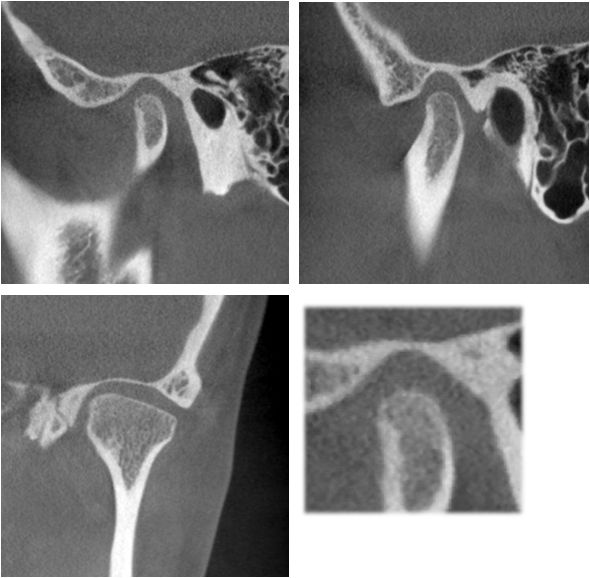

治疗后全景片显示牙根平行度尚可

右侧颞下颌关节髁突表面骨皮质连续均匀,关节间隙均匀。左侧颞下颌关节髁突表面骨皮质增厚,个别吸收点消失,关节间隙较均匀。